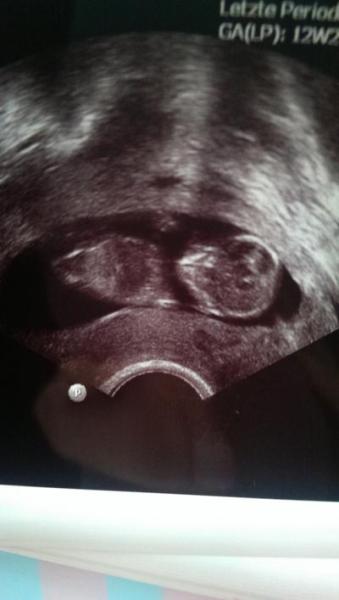

Es war sooooo toll, unser Baby hat getanzt. Ist alles gut und NF ist auch unauffällig. Muss jetzt noch auf die Blutergebnisse warten. Muss jetzt Strümpfe anziehen. Wegen der Blutgerinnungsstörung. Utrogest darf ich jetzt absetzen und wir bekommen eine Überweisung zur Feindiagnostik wegen der Behinderung von meinem Stiefsohn.

Bild zu Bericht FA - Forum für April - Mamis

Wie toll! Schön,dass alles ok ist und das Bild ist ja auch wirklich klasse geworden! Auf das es so weiter geht...

Oh so ein schönes Bild :-) Cool dass der Termin so gut gelaufen ist! Freu mich :-) Dann hoffen wir mal weiter dass bei der Feindiagnostik alles beim Guten bleibt! Genieß den Abend, ConnyJ

Siehste alles gut :-) Ein tolles Foto von eurem Krümel!!!